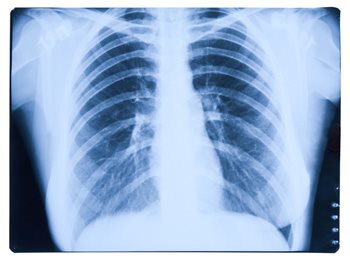

Mesothelioma is known to attack the lining of the lungs, though it can also form in the peritoneum, which is the lining of the abdominal cavity, the pericardium, which is the protective sac around the heart, and the tunica vaginalis.

1. Type of Mesothelioma: There four known types of mesothelioma, pleural, peritoneal, pericardial, or testicular. Depending on the type of mesothelioma, there will be different treatment options available.

4. Smoking: Though mesothelioma is not necessarily associated with smoking or using tobacco products, when it affects the lungs, whether or not the patient is a smoker can affect the possible treatment options. Smoking and its damage to the lungs can further create complications when considering treatment, particularly surgery.